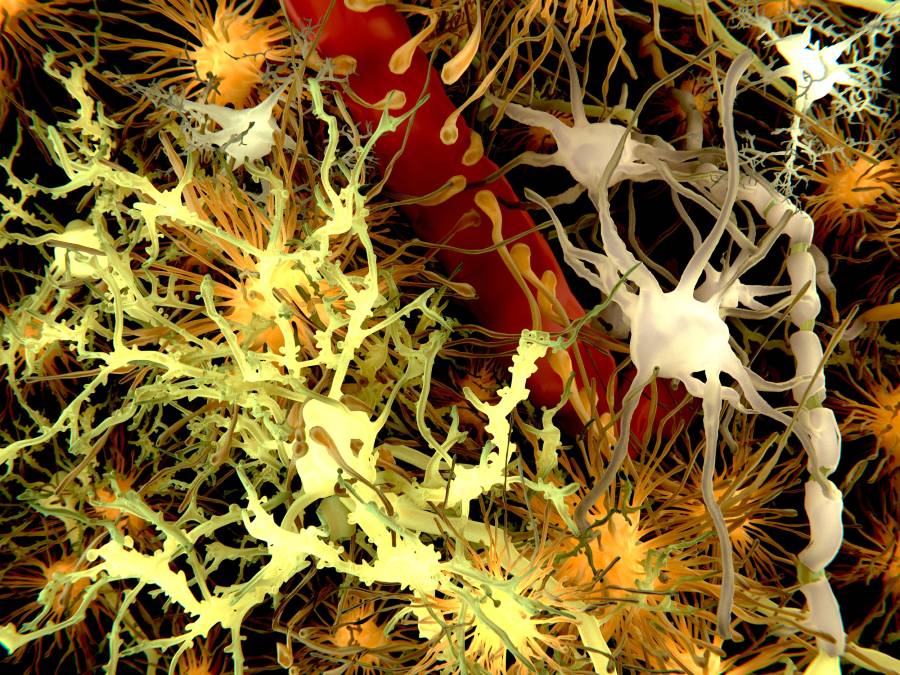

According to the paper, the team led by Jun Nagai, PhD, a principal investigator at RIKEN, investigated the activity of the so-called Fos protein in astrocytes. Traditionally, astrocytes have been thought to have more of a supporting role in the brain. However, when it became clear that engrams—the memory traces that exist in neurons—could not account for stabilized long-term memories, Nagai and his group turned to astrocytes for answers. Neurons produce Fos when activated, as do some astrocytes in response to experiences.

Next, they taught the mice to associate a certain cage with an unpleasant experience. The mice were then removed and returned to the cage several days later. Their reaction showed whether or not they remembered the past event. The results showed that, unlike in neurons, the astrocytes had strong Fos activity only during recall but not during the initial learning. Additional testing showed that the Fos activity in astrocytes required input from neurons in the amygdala that formed the relevant fear-memory engram, as well as from neurons that use noradrenaline as a transmitter.